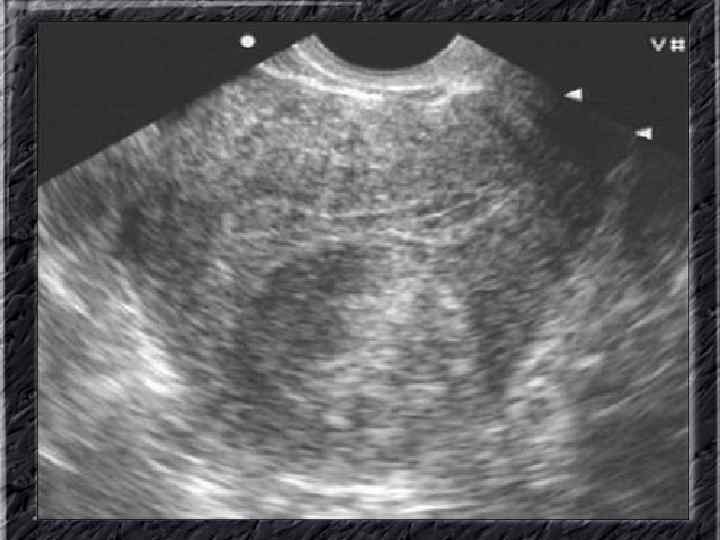

Названия слайдов: • • • Слайд 31. Аденокарцинома эндометрия: образование неправильной формы в дне не увеличенной матки; макропрепарат. Слайд 32. Аденокарцинома эндометрия: бесформенная масса белой опухоли видна по всей поверхности эндометрия матки, вскрытой по передней поверхности, шейка — внизу; макропрепарат. Слайд 33. Нормальная ультразвуковая картина матки и яичников. Слайд 34. Лапароскопия: неизмененные яичники. Слайд 35. Лапароскопия: фолликул на поверхности яичника. Слайд 36. Ультрасонография: жидкостное образование (фолликулярная киста) в параметральной области, однородное, с четкими ровными контурами, кверху и сбоку от кисты определяется ткань неизмененного яичника. Слайд 37. Лапароскопия: фолликулярная киста яичника. Слайд 38. Ультрасонография: киста желтого тела с диффузно неоднородным содержимым средней эхоплотности Слайд 39. Большая эндометриоидная шоколадная киста яичника; макропрепарат. Слайд 40. Ультрасонография: гиперэхогенное содержимое эндометриоидной кисты яичника.

Названия слайдов: • • • Слайд 41. Лапароскопия: эндометриоидная киста яичника. Слайд 42. Лапароскопия: эндометриоидные гетеротопии на поверхности эндометриоидной кисты яичника. Слайд 43. Ультрасонография: поликистозное изменение яичника. Слайд 44. Серозная цистаденома яичника: внешний вид; макропрепарат. Слайд 45. Лапароскопия: цистаденома яичника. Слайд 46. Ультрасонография: папиллярная цистоаденома яичника, содержащая внутри папиллярные разрастания. Слайд 47. Ультраснография: многокамерная киста яичника (муцинозная цистаденома). Слайд 48. Лапароскопия: папиллярная цистаденома. Слайд 49. Ультрасонография: многокамерное жидкостное образование яичника, содержащее полиморфный солидный конгломерат — рак из муцинозной цистаденомы. Слайд 50. Рентгеноконтрастная сальпингография: нормальное наполнение и проходимость обеих маточных труб.

Названия слайдов: • • • Слайд 51. Ультрасонография: интерстициальный и истмический отделы маточной трубы. Слайд 52. Лапароскопия: неизмененная правая маточная труба. Слайд 53. Ультрасонография: многокамерная форма сальпингита. Слайд 54. Лапароскопия: относительно равномерное утолщение маточной трубы при гидросальпинксе. Слайд 55. Лапароскопия: вид маточной трубы при гидросальпинксе. Слайд 56. Гистеросальпингография: неравномерное расширение и деформация маточных труб. Слайд 57. Прервавшаяся трубная беременность: плод; макропрепарат. Слайд 58. Гематосальпингс, развившийся вследствие внутреннего разрыва плодо-вместилища при трубной беременности; макропрепарат. Слайд 59. Лапароскопия: значительное увеличение участка маточной трубы при трубной беременности. Слайд 60. Лапароскопия: скопление крови в полости малого таза в результате трубного аборта.

Названия слайдов: • • • • Слайд 61. Лапароскопия: множественные спайки в полости малого таза женщины. Слайд 62. Лапароскопия: признаки спаечной болезни в полости малого таза женщины. Слайд 63. Лапароскопия: деформация маточной трубы при спаечном процессе в полости малого таза. Слайд 64. Ультрасонография: спаечный процесс в малом тазу. Слайд 65. Ультрасонография: мультифолликулярные яичники. Слайд 66. Ультрасонография: кистома яичника. Слайд 67. Ультрасонография: патолоргия эндометрия. Слайд 68. Ультрасонография: внематочная беременность. Слайд 69. Ультрасонография: внематочная беременность. Слайд 70. Кольпоскопия: кандлилома – папиллома. Слайд 71. Кольпоскопия: кандлидозные бели. Слайд 72. Кольпоскопия: полип шейки матки. Слайд 73. Кольпоскопия: эрозия шейки матки. Слайд 74. Кольпоскопия: экспульсия ВМС.